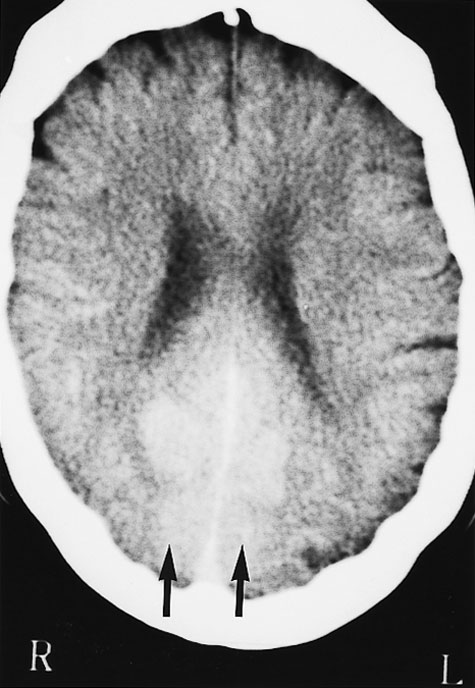

Computed tomography (CT) brain scan was performed three hours after the completion of coronary angiography. No additional contrast was used. The CT brain scan (Box 1) showed marked bilateral contrast enhancement of the occipital lobes and no evidence of a cerebral haemorrhage. Intravenous heparin treatment was commenced. By the following day, she was able to see shapes and shadows but had persistent headache and nausea. A repeat CT brain scan did not show any residual abnormality. During the next 48 hours, her vision progressively returned. She described flashing lights in her right eye and had evidence of right homonymous hemianopia. Magnetic resonance imaging (MRI) showed increased signals in the grey matter of the medial aspect of the left occipital lobe, on a background of longstanding mild ischaemic changes consistent with her age and cardiac risk factors (Box 2A). Magnetic resonance angiography (MRA) showed patency of both posterior cerebral arteries, with dilatation of branches supplying the left occipital lobe (Box 2B). Heparin therapy was ceased, as there was no evidence of acute thromboembolism or acute infarction. She fully regained her vision five days after coronary angiography.

These mechanisms seem possible in our patient, and they were supported by the results of imaging studies. There were bilateral occipital lobe changes when she had clinical cortical blindness (Box 1), representing oedema and passage of contrast across the blood–brain barrier. Cortical blindness is synonymous with bilateral homonymous hemianopia from involvement of the occipital cortex.1 When our patient was recovering and exhibiting right homonymous hemianopia, there were MRI changes in the left occipital gyrus, and differences in the calibre of the vessels on the two sides (Box 2).

1: Computed tomography scan of the patient's brain three hours after completion of coronary angiography, when she had cortical blindness

No additional contrast was given. There is marked bilateral contrast enhancement of the medial aspect of both occipital lobes in a symmetric distribution (arrows).